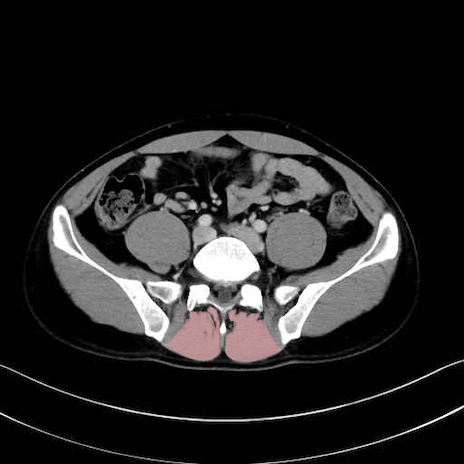

肛門挙筋 (Levator ani)